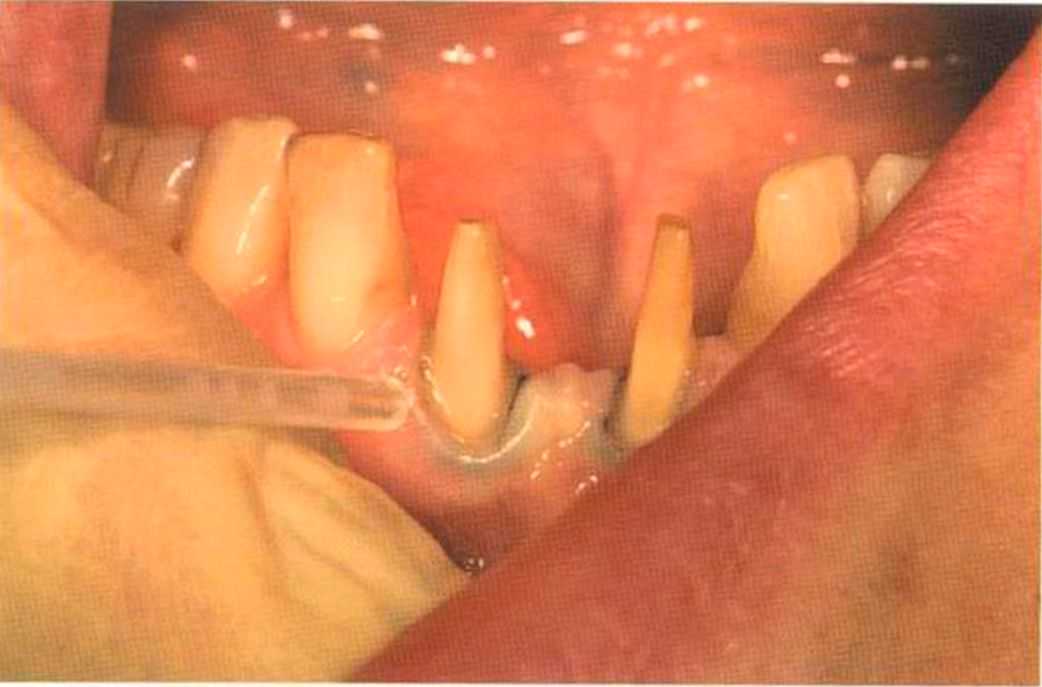

Этот пациент — португалец. Он всю жизнь имел такое положение зубов. Небнорасположенный боковой резец теперь необходимо удалить, а затем воссоздать как эстетику, так и функцию в области фронтальной группы зубов. Планируется изготовить коронки In-Ceram в области 11 и 21 и соединить их вместе из-за увеличивающейся подвижности зубов.

Препарирование, проводимое доктором Риссе, оценивается как очень сложное. Режущие края центральных резцов сильно дивергируют, что создает неудобство при формировании хорошего уступа.

Фото сверху и слева: отличный результат препарирования зубов с уже уложенными нитями для снятия оттиска.